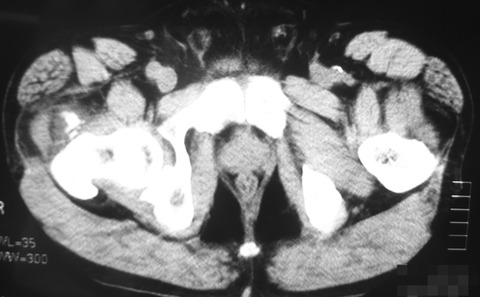

熱発や股関節の伸展制限はありませんでした。圧痛点が大転子の前方にあったのでCTを施行したところ、大転子部の高位の大腿骨前面に石灰化を認めました。

良く見ると中殿筋の腫脹も認めます。血液生化学データはWBC 12000, CRP 6.3と炎症所見の亢進を認めました。ただ、疼痛はかなりきついものの、ご本人に重篤感はありません。